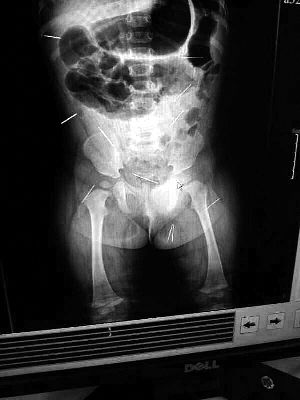

山東聊城11個月女嬰萱萱(化名)疑似被人以12根鋼針插滿臀部、腹腔等部位,昨天在兒童醫(yī)院會診后,醫(yī)生稱3根針靠近胸腔最危險,首批先行取出,預計將在下周二手術。孩子父母稱孩子一直由家人照顧,自家與他人并無冤怨。山東警方表示正在偵破中,不便透露案情。

“要不是當初那幾個紅點,可能到現(xiàn)在我們還不知道孩子身體里有鋼針!”昨天,在兒童醫(yī)院住院處,萱萱爸爸范先生稱,日前原本很愛笑的萱萱突然變得有些焦躁,一抱起來就哭,孩子母親偶然間在萱萱屁股上發(fā)現(xiàn)了幾個小紅點兒,原以為是蚊蟲叮咬,就醫(yī)結果卻讓人不寒而栗?!搬t(yī)院拍出的片子上,萱萱的體內(nèi)有12根鋼針,插滿臀部、腹腔、骨盆等各個部位?!狈断壬榻B,因為鋼針已深入體內(nèi),要是孩子不哭鬧,他們很難發(fā)現(xiàn)。

北京晨報記者了解到,目前體內(nèi)的12根鋼針多分布在孩子的臀部,一根在腹部,其余3根在胸腔附近,其中一根很接近心臟?!耙驗楹⒆犹?,醫(yī)生們害怕取針的時候?qū)λ斐蓚Γ谛厍桓浇?針可能會威脅她的生命”。